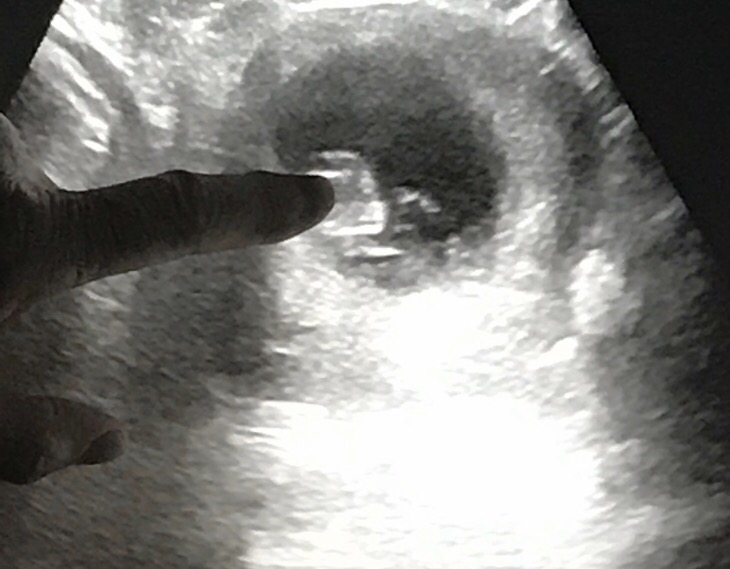

Ten Week Appointment

Whenever I have a prenatal appointment, the hours before it are always ones of joy, excitement and curiosity. Today’s appointment went great and may be my favorite among our visits so far.